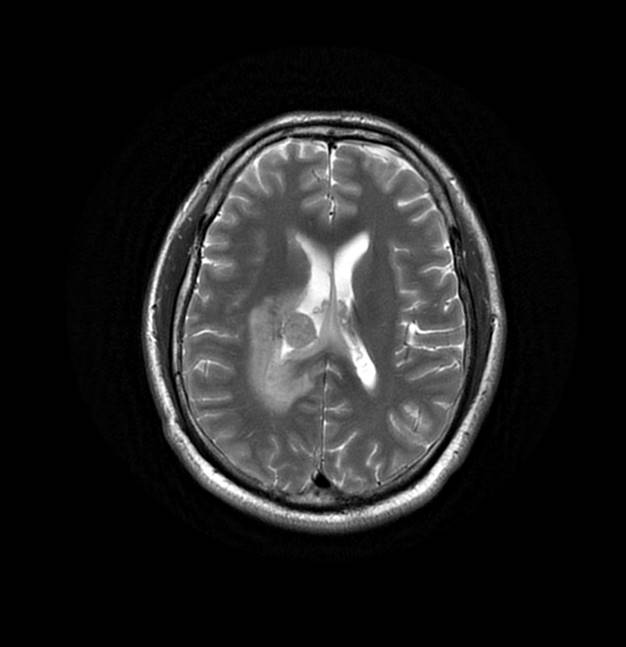

磁共振影像圖

圖1

圖2

圖3

圖4

MR診斷:右側(cè)側(cè)腦室三角區(qū)及側(cè)腦室旁占位,考慮惡性腫瘤可能,間變型腦膜瘤?轉(zhuǎn)移瘤?

MR鑒別診斷

常規(guī)MR檢查是診斷腦膜瘤的有效手段,可以明確腫瘤發(fā)生的部位、形態(tài)和數(shù)目等特征以及病變向鄰近腦實(shí)質(zhì)侵犯的程度和范圍,典型腦膜瘤呈等或(和)稍長(zhǎng)T1、等或(和)稍長(zhǎng)T2信號(hào),??娠@示完整的包膜,增強(qiáng)掃描因腫瘤內(nèi)部新生血管通透性不同呈不同程度強(qiáng)化,由于腫瘤組織的強(qiáng)化程度與腫瘤的惡性程度不完全一致,導(dǎo)致MR常規(guī)檢查在腦膜瘤分級(jí)分型方面仍存在一定的困難。擴(kuò)散加權(quán)成像( diffusion weighted imaging,DWI) 及表觀擴(kuò)散系數(shù)( apparent diffusion coefficient,ADC) 被廣泛用于腦腫瘤的分級(jí)、分子分型和腫瘤侵襲性預(yù)測(cè),并取得了良好的性能。目前,對(duì)于非典型腦膜瘤腦實(shí)質(zhì)侵犯的診斷的金標(biāo)準(zhǔn)依賴于組織病理學(xué)。